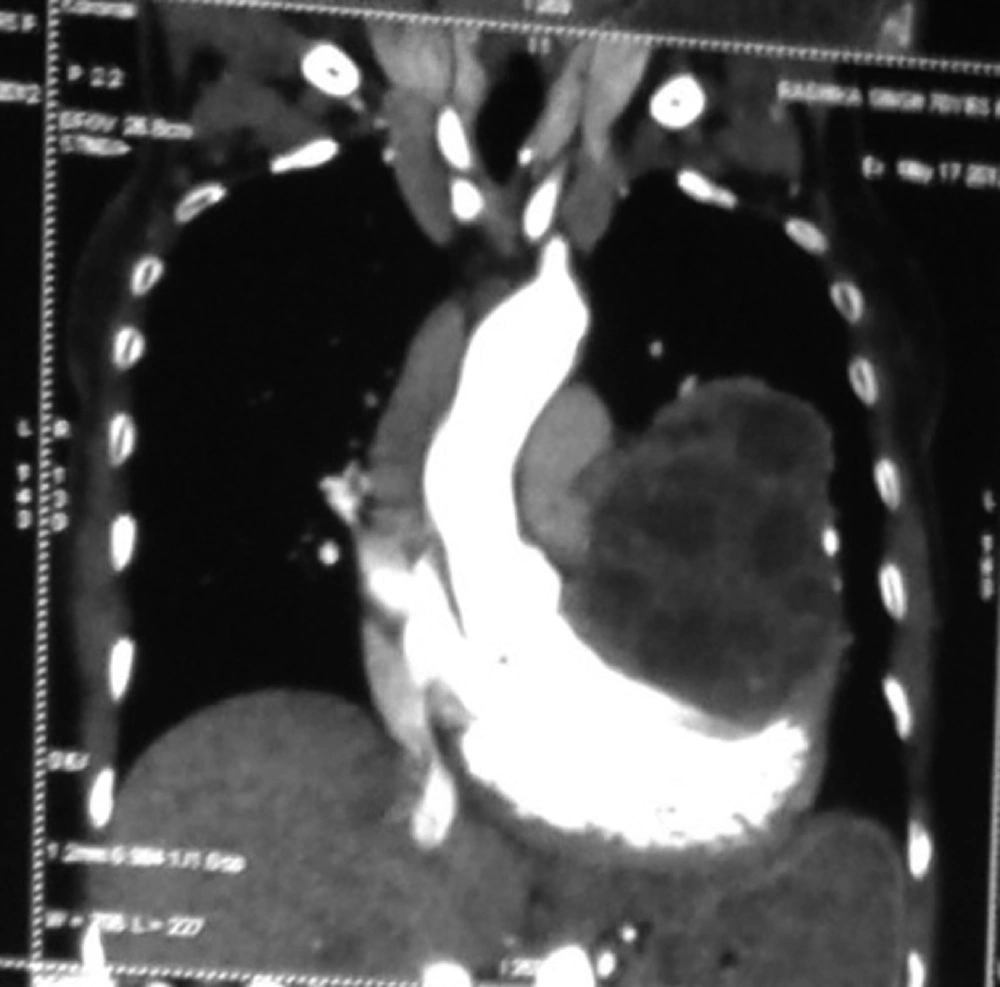

In June 2011, a 60 year old woman was admitted to our emergency room with complaints of shortness of breath, palpitation, chest pain and progressive dyspnea. She had history of dyspnoea on exertion and orthopnea too. She had no history of trauma or major illness. On her physical examination, arterial blood pressure was 135/90 mmHg, heart rate was 110 beats per minute, SpO2 94% on room air and respiratory rate was 24 breaths per minute. On auscultation, the lungs were normal and no cardiac murmur, no JVP raised or gallop rhythm was noted. Cardiac enzymes, biochemical analysis, and complete blood count were normal except for eosinophilia. Chest radiography noted that cardiomegaly with bulging left heart boarder at admission (Figure 1). Electrocardiography (ECG) showed normal sinus rhythm with poor progression of R wave in lead v4, v5, and v6 and no changes in ST segment. Her myocardial-specific enzyme values were found in the normal range. Transthoracic echocardiographic investigation showed a large multicystic mass (size 77 × 57 mm) seen intrapericardially extending from left ventricle lateral wall to pericardial sac causing pressure effect on left ventricle. The abdominal ultrasonography revealed intracardiac hydatid and other cystic lesion either in the liver or other abdominal organs were not found. Contrast-enhanced CT confirmed the presence of a well-defined, thin-walled, homogeneous multiple cardiac hydatid cyst with internal trabeculae arising from pericardium with adjacent structure (Figure 2). Results of serologic tests for hydatidosis (indirect hemagglutination tests) were positive for E. granulosus, and marked eosinophilia was present too. After diagnosis, the patient was scheduled for surgery with the diagnosis of cardiac hydatid cyst. Patient was taken into the operation theatre and monitoring including ECG, pulse oximetry and non-invasive blood pressure were established and general anesthesia was performed with opioid-muscle relaxant technique after that established left radial artery cannulation for beat to beat blood pressure monitoring and internal juglar vein cannulation for central venous pressure monitoring. The pericardium was accessed through left lateral thoracotomy, accessing to the left mediastinal area, a solitary cystic lesion with a well-defined border was visualized in the pericardium adjacent to the left ventricle and the pericardial cyst was surgically removed (Figure 3). Patient’s trachea extubated and Intraoperative and postoperative hemodynamic status was maintained and within normal limits. Post-operative pain managed with inter costal block with 0.5% of bupivacain plain, inj. tramadol and diclofenac sodium I.M. Pathologic examination of the specimen was shown with hydatid cyst.